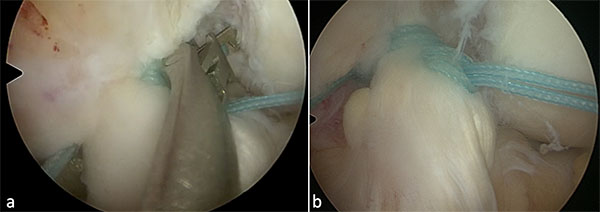

En primera instancia se observan ambos meniscos, el cartílago articular y, en caso de ser necesario, se tratan Posteriormente se evalúa la lesión del LCA para determinar que la lesión sea completa y se localice dentro del 10% proximal, con buena calidad de fibras remanentes, y que las mismas puedan ser reducidas al sitio de inserción en el fémur. Se puede confirmar la inestabilidad realizando cajón anterior y observando el desplazamiento de las fibras remanentes del LCA (fig. 1, video 1). Para una mejor visualización se puede realizar un portal mid-patelar de Patel.15

Figura 1: Ligamento anterior conservado practiramente en su espesor completo (a), con gran desplazamiento al realizar maniobra de cajon anterior (b).

2. Sutura de ambas bandas del LCA

Utilizando una pinza grasper o toma hilo se confirma que el ligamento sea reducible en su inserción femoral (el remanente del LCA puede presentar cierta retracción que no permita su reparación) (fig. 2, video 2).

Figura 2: Utilizando una pinza tipo grasper (a) o toma hilo se confirma la reducción de las fibras del LCA para su posterior reparación.

A través del portal medial y lateral con una pinza de sutura (Scorpion,Arthrex, se realizan 2 puntos tipo lazo con sutura ultra-resistente al LCA, uno a la banda Antero-Medial y uno a la banda Postero-Lateral (fig. 3, video 3) intentando tomar la mayor cantidad de tejido ligamentario.

Figura 3: Utilizando una pinza de suturar (a) se realizan 2 puntos tipo lazo con sutura ultra-resistente al LCA, uno a la banda Antero-Medial y uno a la banda Postero-Lateral (b)